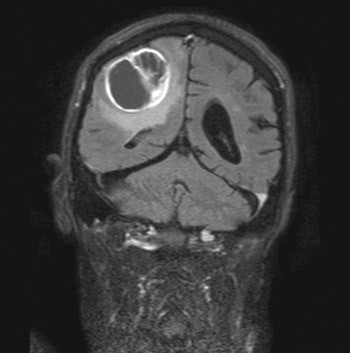

One year later he developed rigidity in arms and legs during a few weeks. He needed help to dress and undress and was therefore admitted to a nursing home before he consulted a neurologist. A clinical neurological examination revealed marked rigidity axially and in arms and legs. He had difficulty getting up from a chair and walked very slowly and unsteadily. No abnormal reflexes or spasticity were found during the examination. His condition was interpreted as increasing parkinsonism and the levodopa dose was increased to 400 mg per day. However, he became worse with this dose and three weeks later he was admitted to the neurological department. The personnel in the nursing home reported that he had been unable to walk the last two weeks before admission. The man’s regular general practitioner had in the meantime increased the levodopa dose to 600 mg per day without improvement. Upon admission he was tired but opened his eyes when spoken to. He was oriented about time and place. It was difficult to perform an examination of strength, but he managed to sit without support. His reflexes and sensibility results were normal. There were no signs of spasticity or abnormal reflexes at the time of admission or with clinical follow-up examinations during his stay. MR of the brain showed a contrast-filled tumour of 4 × 6 × 4 cm in the right parietal region (fig 1). He was operated and a histopathological examination showed glioblastoma multiforme. The patient died a few weeks later.

Figure 1  MR of the brain showed 4 × 6 × 4 contrast-filled tumour in the right parietal region. Histological examination…

Figure 1 MR of the brain showed 4 × 6 × 4 contrast-filled tumour in the right parietal region. Histological examination showed glioblastoma multiforme